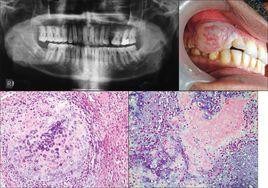

④X線檢查成骨性骨肉瘤骨密度增高,有日光放射狀或蔥皮樣改變,溶骨性骨肉瘤則表現為蟲蝕樣溶骨改變。

④X線檢查成骨性骨肉瘤骨密度增高,有日光放射狀或蔥皮樣改變,溶骨性骨肉瘤則表現為早蝕樣溶骨改變。

⑤病理組織學檢查確診。

①X線檢查

②CT掃描:顯示病變在髓腔內的範圍、腫瘤鈣化、骨皮質和軟骨組織情況 。